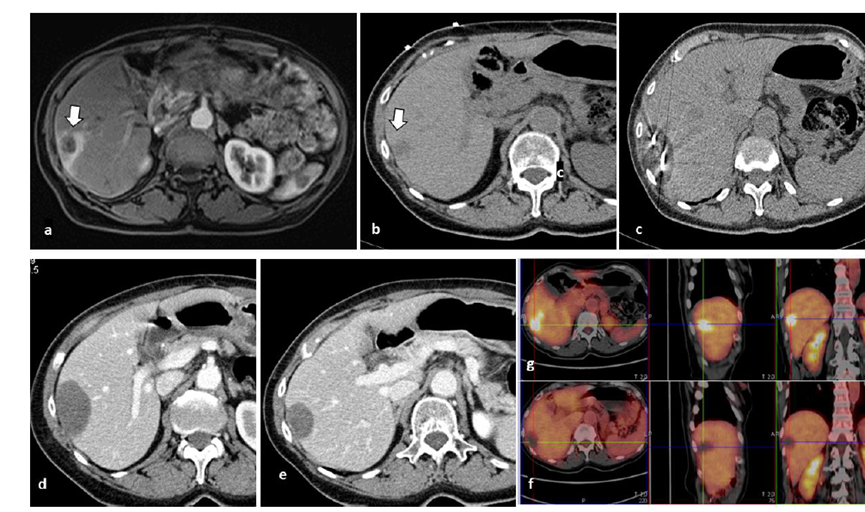

冷凍消融膽囊附近腫瘤病灶

(A)動脈期 MRI 顯示膽囊附近有外周增強(qiáng)病變(箭頭)。

(B)手術(shù)過程中 CT 顯示冷凍探針位于病灶內(nèi)。

(C)消融后,術(shù)后 1 個(gè)月CT 顯示完全消融(箭頭)。

(A)動脈期CT圖像顯示有一個(gè)包膜下結(jié)節(jié)(箭頭)。(B)門靜脈期CT圖像顯示病灶區(qū)(箭頭)。(C) 在手術(shù)過程中的CT顯示一個(gè)冷凍探針位于病灶內(nèi)。(D)消融后,術(shù)后1個(gè)月影像CT顯示完全消融。患者在手術(shù)及住院期間無并發(fā)癥及重大并發(fā)癥發(fā)生。隨訪時(shí)間中位數(shù)為7個(gè)月(范圍:3-12個(gè)月),隨訪期間患者無局部腫瘤進(jìn)展或死亡。

技術(shù)成功率為100%,本研究中77.8%(7/9)的患者達(dá)到了完全消融,輔助局部治療后,所有患者均完全消融。

膽囊附近轉(zhuǎn)移灶(來自子宮頸癌)的冷凍消融術(shù)(A)門靜脈期 CT 圖像顯示膽囊附近有病變(箭頭)。(C) 手術(shù)過程中CT 顯示冷凍探針位于病灶內(nèi)。(D)消融手術(shù)后 1 個(gè)月CT 顯示完全消融。